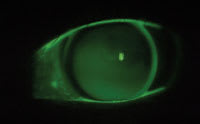

Figure 1. Fluorescein pattern of LD's translating GP design. |

In 1999 we switched LD into a GP translating design originally in Boston ES, now in Boston EO (Bausch & Lomb) material in the following prescription: OD 7.50 –5.50 9.5/9.2 4.5 segment height 1.5 prism +2.50 add 20/20 distance and near, OS 7.50 –4.75 9.5/9.2 4.5 seg. ht. 1.5 prism +2.50 add 20/20 distance and near (Figure 1). Her manifest refraction was OD –6.00 –1.00 x 075 20/20 +2.75 add Jaeger 1, OS –5.25 –1.25 x 105 20/20 +2.75D add Jaeger 1. Her Ks and topography were OD 45.25/46.00, OS 45.00/46.00, clear mires.